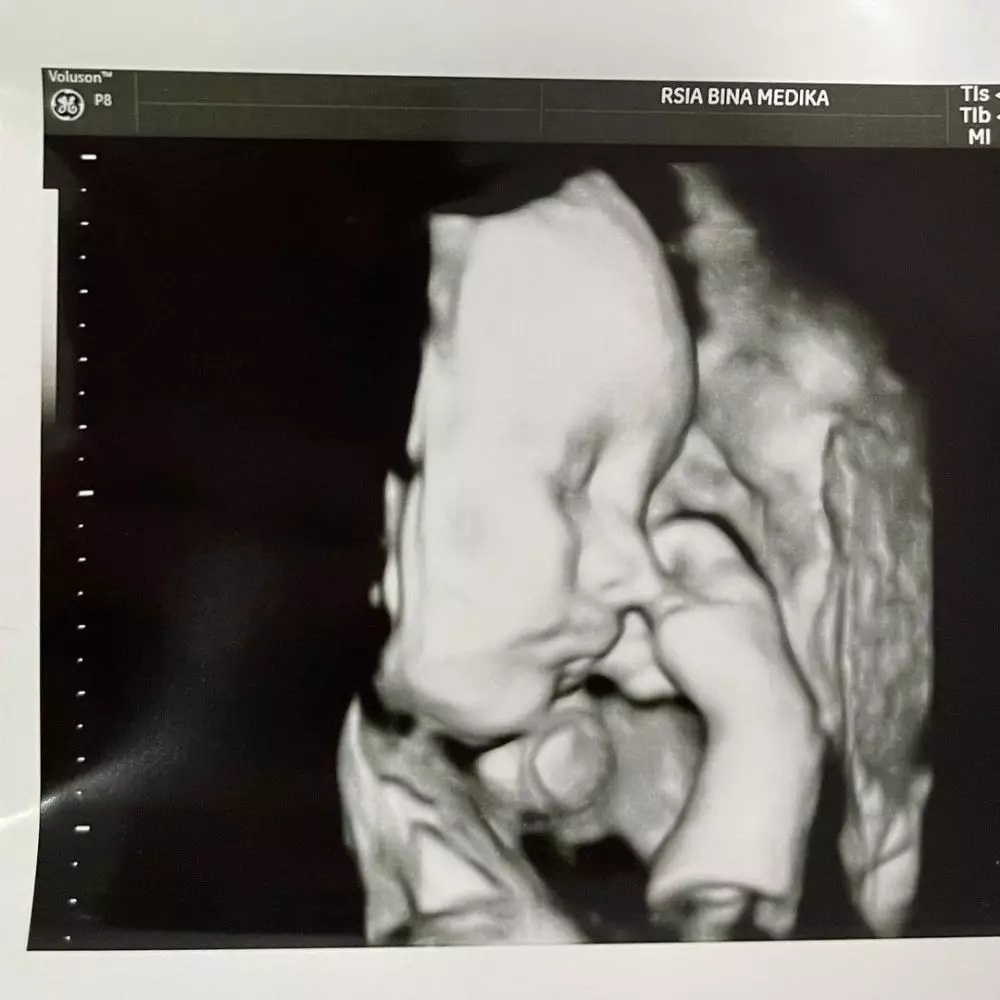

Tapi kami sangat bersyukur baby Anzel semua organnya baik & bagus. Tapi masih terus harus dipantau di ruang NICU. Jadi mama belum bisa peluk langsung. Ohya ini photo USG beberapa jam sebelum lahir. Maaf om tante online belum bisa kasih liat keadaan bao bao skg karena masih dirawat dalam inkubator," ungkap Audi dalam unggahannya.

1. Audi mengungkapkan foto USG ini diambil beberapa jam sebelum baby Anzel lahir.

foto: Instagram/@audimarissa